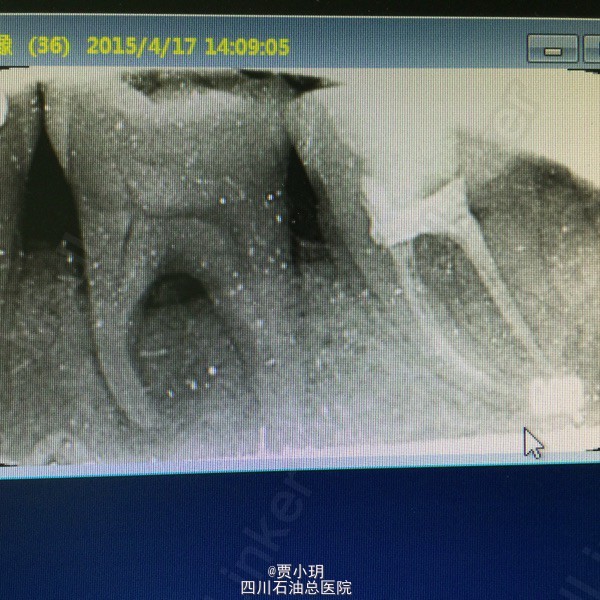

查体:口内见36颊侧颈部充填物,松动II度+,垂直叩痛(+),侧方叩痛(++),冷诊(+),热诊(++),颊侧牙周袋深约为5mm,可探及根分叉。X线示36近中根及根分叉周大面积阴影,根分叉处骨吸收影像。

诊断:36牙周牙髓联合病变 处理:1、局麻下,行36开髓,封失活剂。同期行36牙周治疗,包括牙周洁治,根面平整,双氧水反复冲洗并上药。 2、一周后复诊,36常规行根管治疗,行MTWO根扩。 3、一周后复诊,36再次行牙周刮治,冲洗,上药。 4、一周后复诊,36行根充,复合树脂充填。观察随访,择期行牙冠修复。